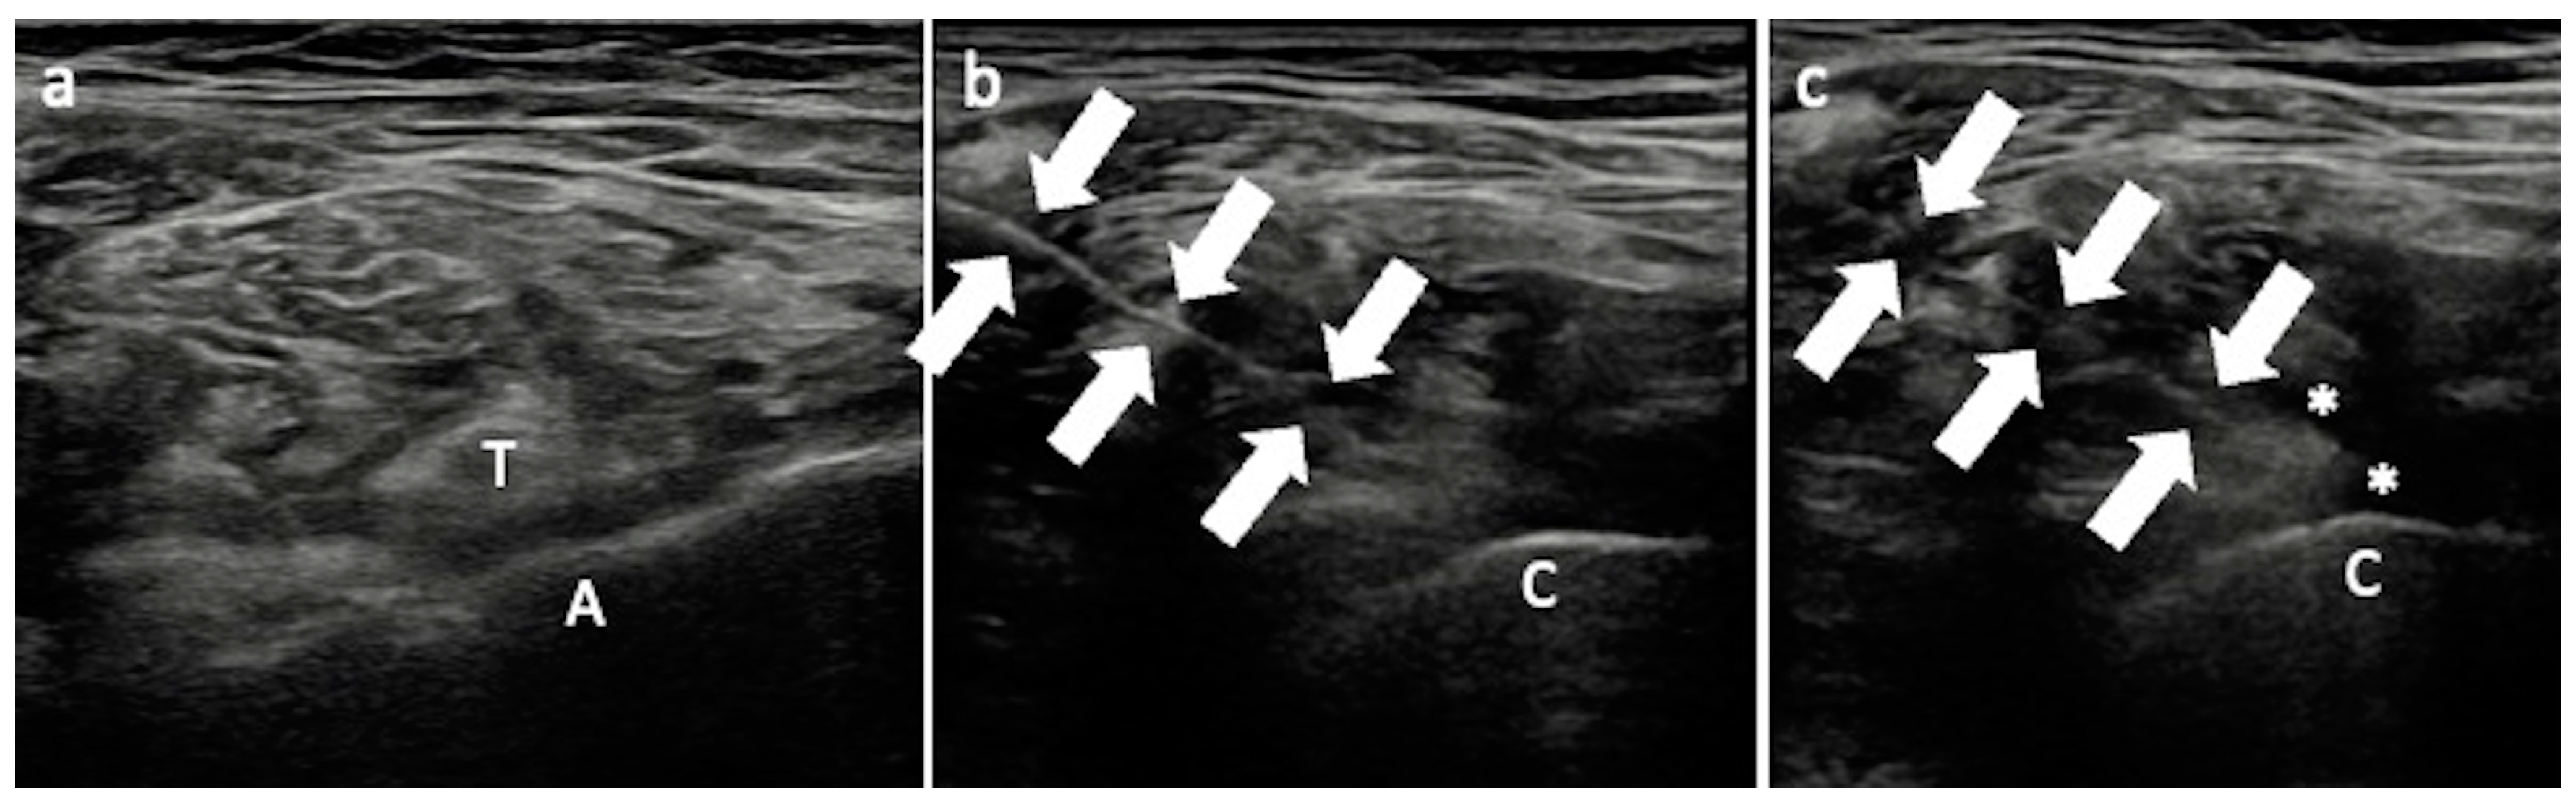

3.2. Iliopsoas Tendinopathy

Technical Considerations